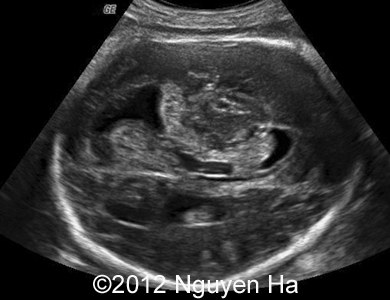

Figure 8-15: 4 days later; image 1-4 suggesting a middle cerebral artery infarction with formation of schizencephaly, no more cortex at the level of the insula.

A 30-year-old woman (G1P0), with unremarkable family history, presented to our unit at 36 weeks of her pregnancy. She did not undergo any previous screening tests. Our examination revealed unilateral hypoechoic inhomogeneous mass within cerebral parenchyma. Our initial diagnosis was teratoma, but repeated exam after four days showed structural changes and different echogenicity of the mass and so our final diagnosis was cerebral hemorrhage. The findings were confirmed by MRI scan.